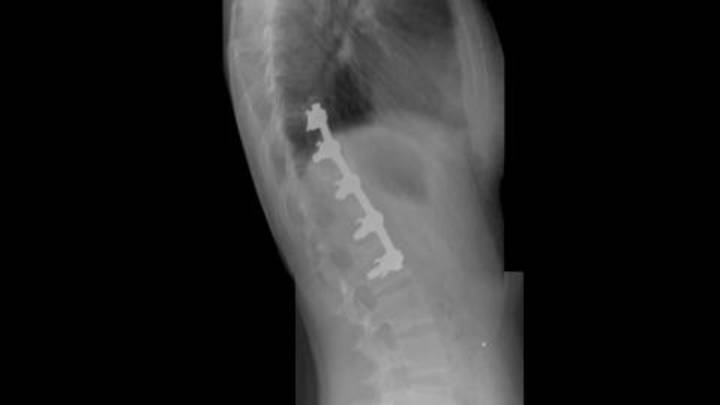

Learn Stacy Lewis' incredible story of overcoming scoliosis as an 11-year-old girl to becoming one of the top players on the LPGA Tour.